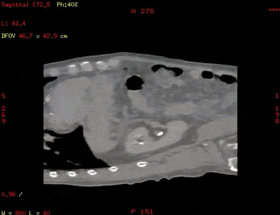

Smart D4D:腹部4D成像